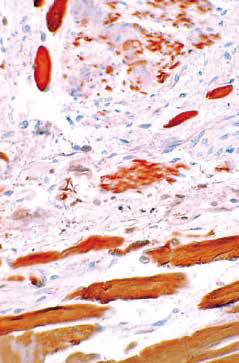

近端食管。固有肌层由平滑肌束和横纹肌束混合而成。

肌红蛋白抗体染色显示混合存在的平滑肌(弱着色)和横纹肌(强着色)。

肌红蛋白染色切片的高倍镜图片,显示核位于外周的典型横纹肌。

虽然存在两种不同类型的肌肉,但它们可作为一个整体发挥功能。两种肌纤维层之间可见Auerbach神经丛和其相关的Cajal间质细胞,间质细胞也可见于固有肌层内。